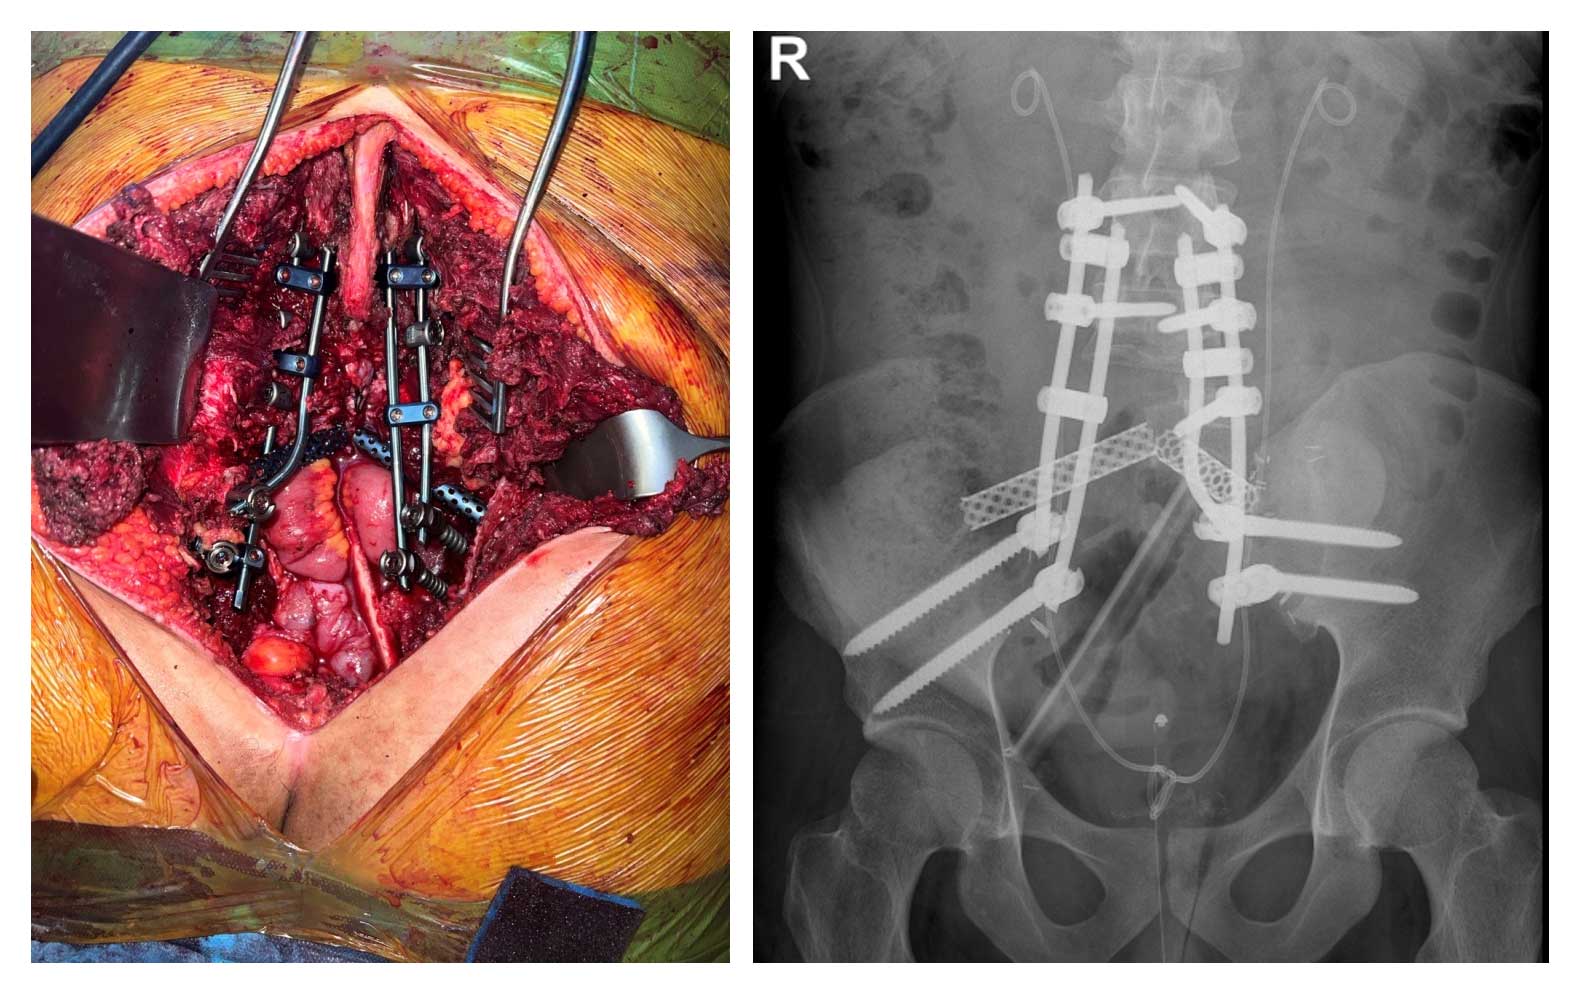

Hasta neoadjuvan kemoterapi sürecini tamamladıktan sonra iliak kanat posterior ve L5 vertebra yarısı dahil total sakrektomi gerçekleştirildi. Çıkarılan tümörlü bölgenin ardından omurga ve pelvis stabilitesinin yeniden sağlanması amacıyla titanyum kafes, fibula grefti ve lumbopelvik fiksasyon kullanılarak rekonstrüksiyon işlemi başarıyla uygulandı.

Ameliyat Esnası ve Sonrası: Total sakrektomi sonrası fibula, titanyum kafesler ve lumbopelvik fiksasyon ile yapılan rekonstrüksiyon işleminin klinik ve röntgen görüntüsü.